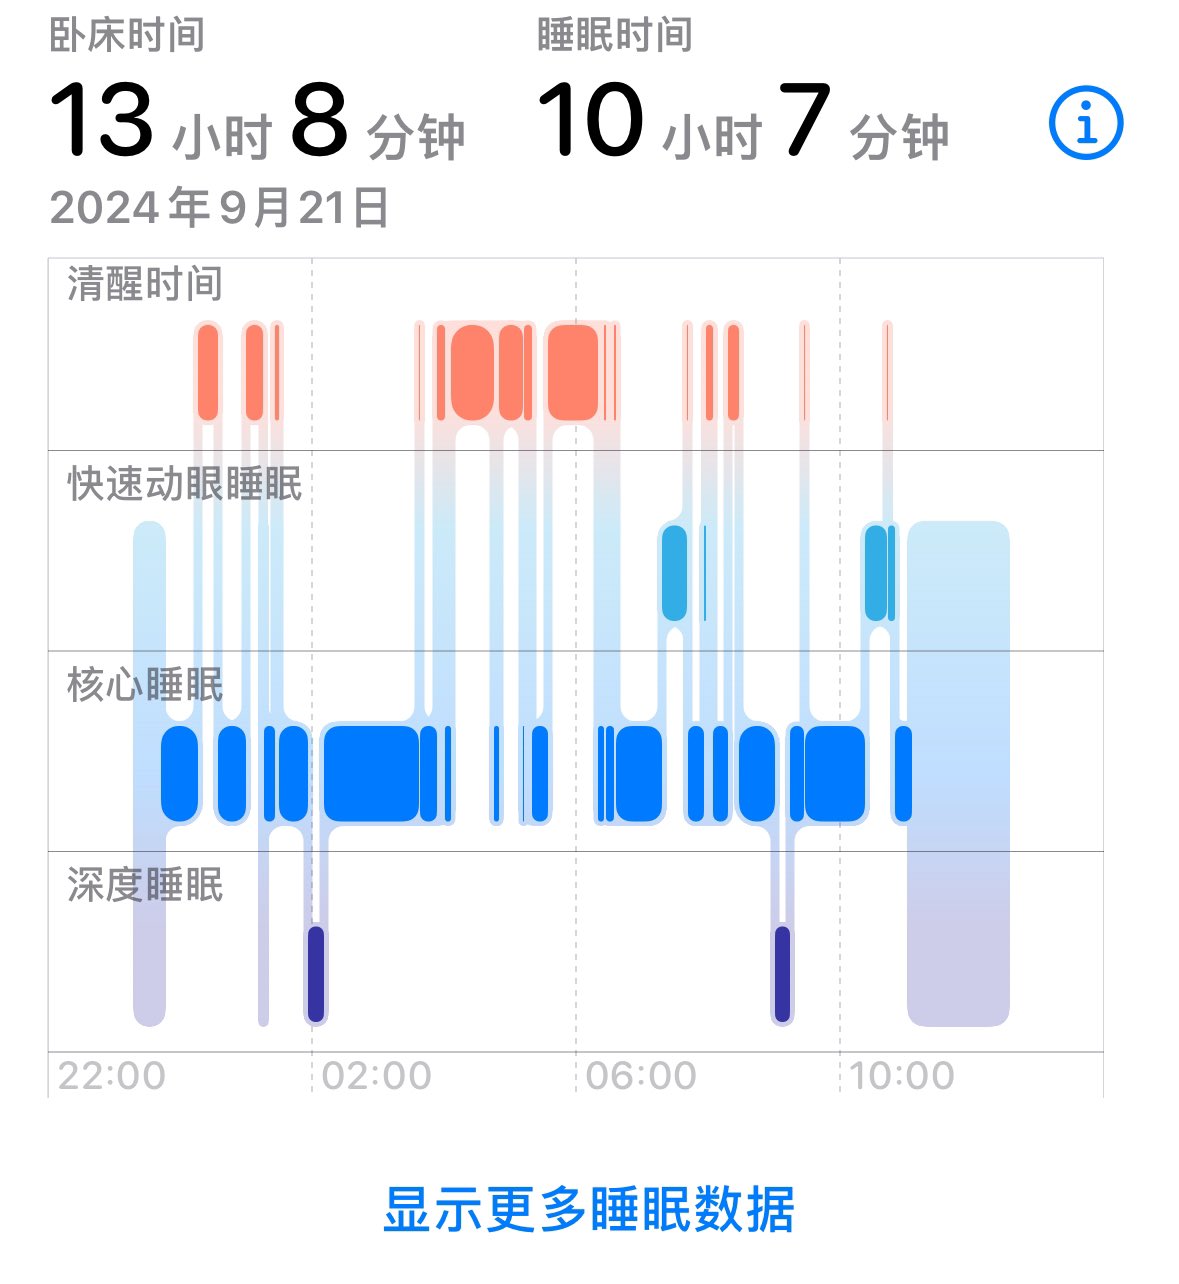

-睡眠障碍:包括严重失眠、REM周期紊乱。

-睡眠障碍:包括严重失眠、REM周期紊乱。

此剂量下对睡眠的改善作用,增加了慢波睡眠且没有影响rem,精力恢复+